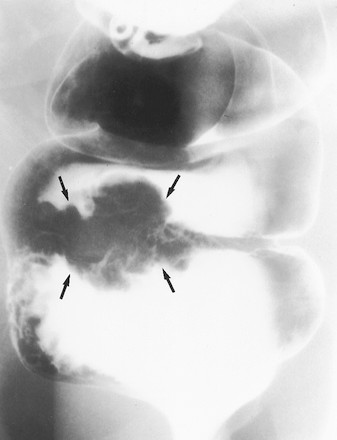

Ung thư biểu mô hình khuyên hay phát triển ở vùng sigma nhất nhưng cũng có thể thấy ở đại tràng xuống, đại tràng ngang, và đại tràng lên. Trái lại, chúng không xảy ra ở manh tràng và trực tràng do khẩu kính của các đoạn đó lớn. Các tổn thương hình khuyên biểu hiện trên phim cản quang baryt bằng hẹp chu vi lòng ruột, với sự phá hủy niêm mạc, với các bờ nhô lên như dải đá ngầm (Hình 11, 12). Chủ yếu phải quan sát các quai ruột tách nhau, nếu quai ruột chồng nhau có thể không quan sát thấy tổn thương (Hình 12).

Hình 11. Hình cản quang kép khu trú, bệnh nhân nằm ngửa phát hiện hai ung thư biểu mô tuyến đồng thời. Khối ung thư biểu mô hình khuyên ở đoạn cuối đại tràng ngang đặc trưng bởi sự phá hủy niêm mạc và các bờ nhô lên hình đá ngầm (mũi tên trắng, thẳng). Khối ung thư biểu mô tuyến thứ hai dạng polyp (mũi tên đen) nằm ở đoạn đầu đại tràng ngang. Bệnh nhân này cũng có một polyp tuyến (mũi tên trắng, cong) ở sát bờ ngoài tổn thương hình khuyên.